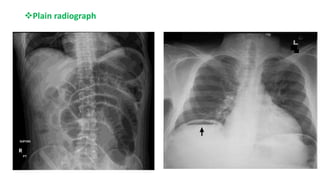

๏ถPlain radiograph

๏ƒ˜ CT angiography or MR angiography 1st line for a definite diagnosis.

๏ƒ˜CT is performed without oral contrast as it can obscure mesenteric vessels and

bowel wall enhancement.

๏ƒ˜MRA is more sensitive; ideal for patients with allergies.

๏ƒ˜CT can show focal or segmental bowel wall thickening, intestinal pneumatosis,

bowel dilatation, or solid organ infarction.

๏ƒ˜Lack of enhancement of arterial vasculature with contrast.